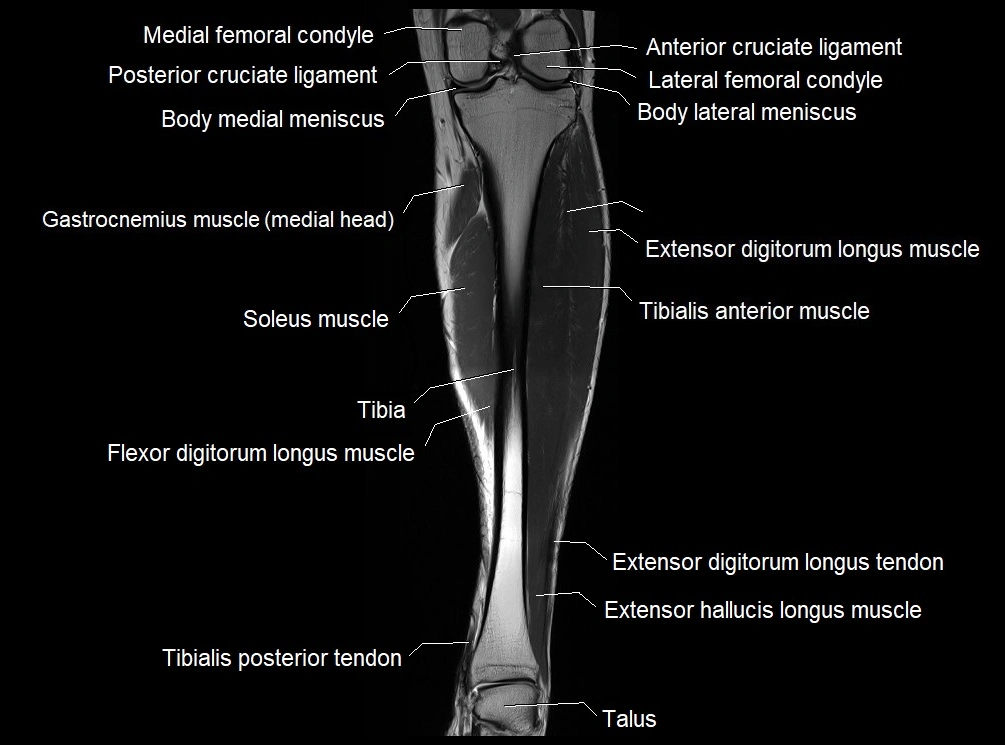

MRI image